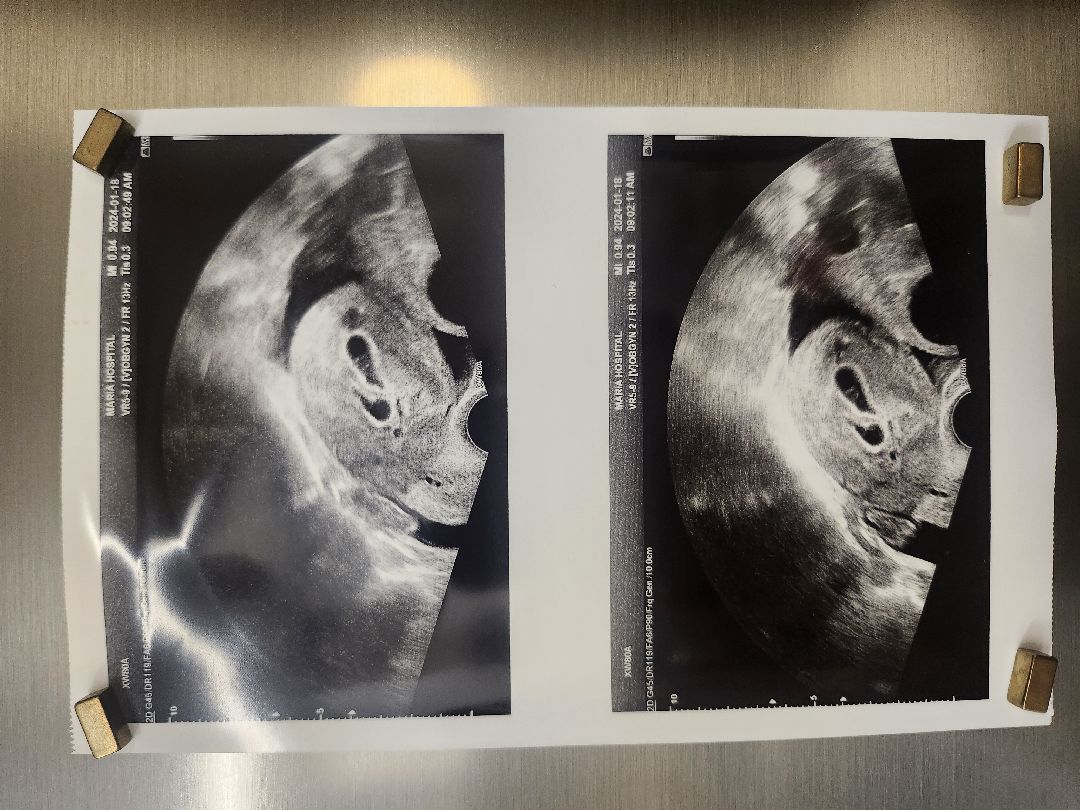

초음파보니 쌍둥이에요!!

시험관했어요. 증상들이 쎄서 쌍둥이아닐까 하는 생각이 있었는데 진짜 쌍둥이였어요 ㅠㅠ 5주4일차 난황까지 잘 보고왔네요. 벌써부터 분만병원 조리원.. 인테리어며.. 고민이 많네요. 7-12월 서울 쌍둥이 소통방이 없어서 대화방 만들어놨는데 쌍둥이예비맘 있으면 소통하실분계세요?? https://open.kakao.com/o/g3qFNs4f